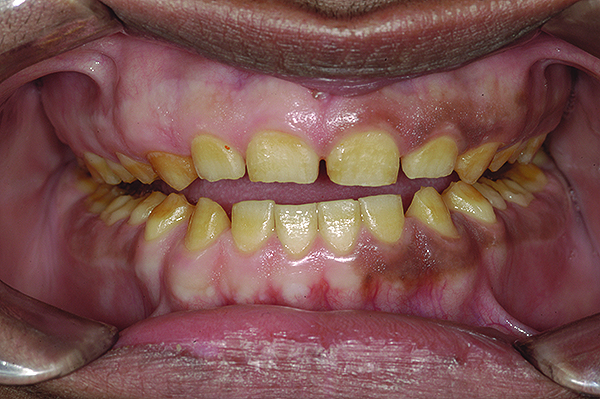

Figure 5. Preoperative 1:1 retracted frontal view.

Figure 5

A thorough clinical examination and analysis were carried out to assess the esthetic and functional problems of the patient (Figure 2 through Figure 7). The medical history was non-contributory, except for mild leukoderma. Temporomandibular joint (TMJ) function was within normal range.

Mounted study casts were used to evaluate occlusion. The relevant findings were as follows2: Facial analysis revealed a canted maxillary occlusal plane and canted dental midline. Dentolabial analysis showed that the maxillary incisors were not adequately visible during repose; it also revealed a reverse smile line, as well as a wide smile showing 12 teeth. Results from the phonetic analysis were that “F” and “V” sounds revealed upper incisal shortening, “M” and “S” pronunciation disclosed a diminished vertical dimension of occlusion (VDO), and “E” sounds showed severe shortening of incisors. Dental analysis revealed thick biotype, asymmetry and inappropriate location of gingival levels and zenith, incorrect axial inclinations, a displeasing width-to-length ratio, and pitted surfaces on most teeth. Interproximal decay was evident on several posterior teeth, as revealed by radiographic analysis. Finally, occlusal examination indicated discrepancy between maximum intercuspation (MIP) and centric relation (CR) as well as a lack of anterior guidance/posterior disclusion.